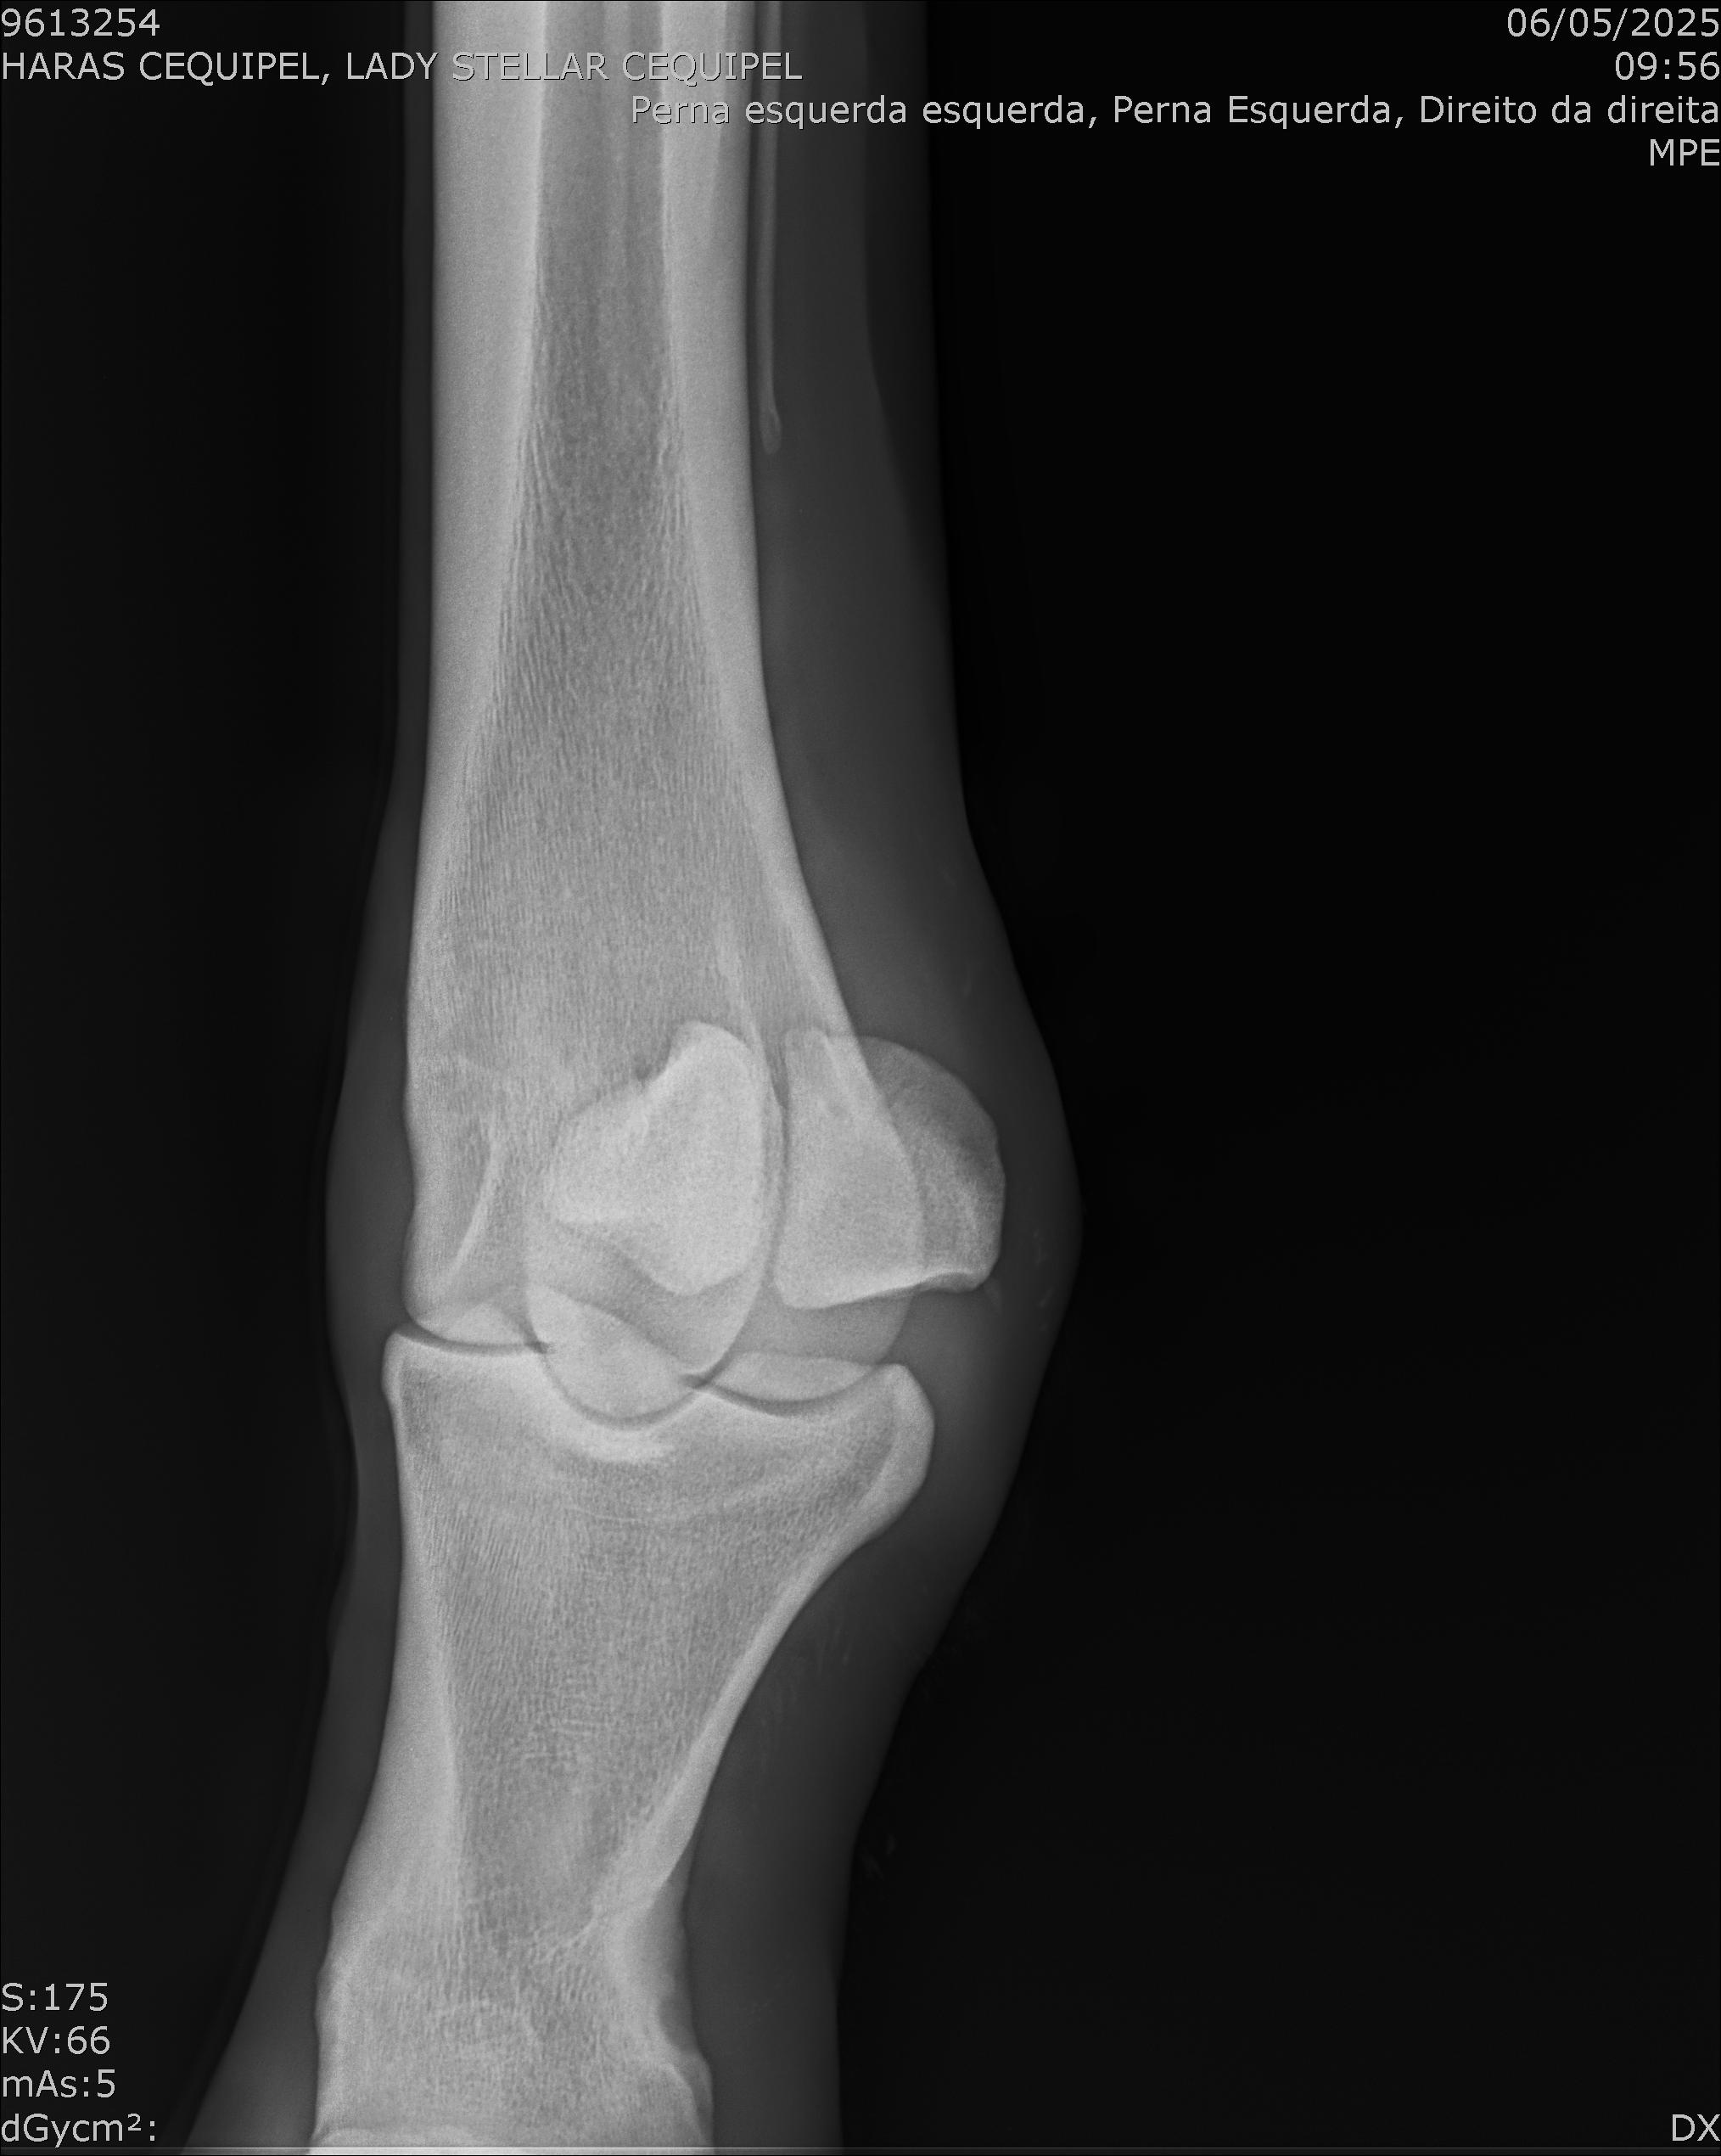

:: RAIOS-X DO LOTE